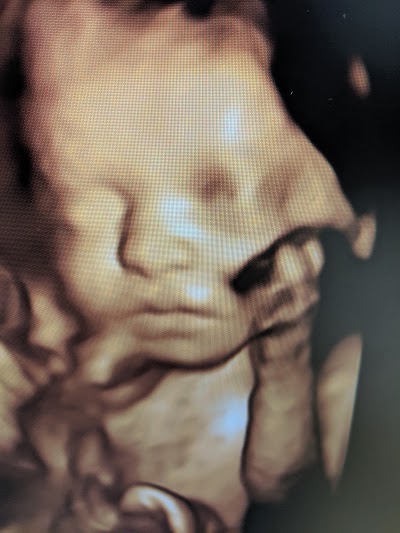

. 1 review of Sweet Baby Face Elizabethtown Came into Sweet Baby Face to have 30 week 3D ultrasound. Sweet Baby Face hd 3d 4d ultrasound. Make Appointment Call 502 509-1003 Get directions.

Sweet Baby Face in the city Elizabethtown by the address 120 Drexler Cir Elizabethtown KY 42701 United States. 1 review of Sweet Baby Face Elizabethtown Came into Sweet Baby Face to have 30 week 3D ultrasound was greeted immediately by Melissa with a friendly smile and hello. Get directions reviews and information for Sweet Baby Face in Elizabethtown KY.

WE SUGGEST THE PINK AND BLUE PACKAGE FOR GENDER. Sweet Baby Face ultrasound clinic brings images of your baby to life. 3d ultrasound is a relatively new technology.